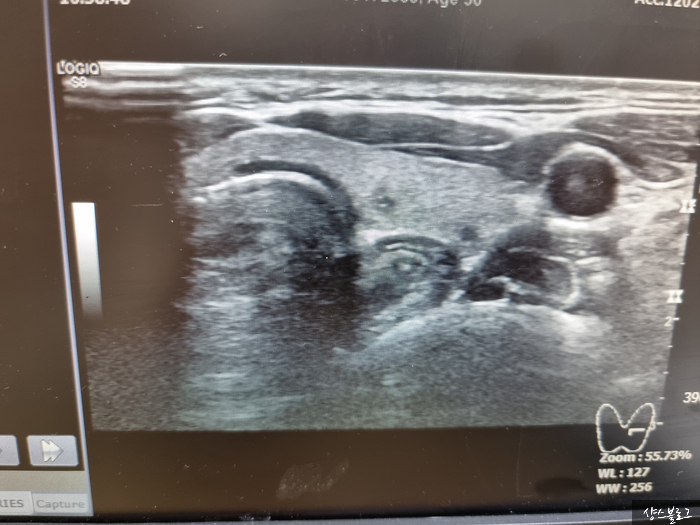

<갑상선 초음파>

<갑상선 초음파> 비에비스나무병원은 건강검진 전문병원입니다.건물 리모델링을 중간에 하고 나니 더 깨끗해졌어요. 시설은 검진 전문이어서 그런지 오후 늦게 갔더니 너무 조용하더라구요.코로나 때문에 검진도 연기되겠네요.저도 한 2달 더 미루고 왔습니다3년 전에 검사했을 때 몇 가지 의문이 있었지만 없어진 것도 있고, 아직 남아있는 것도 있습니다.둥글고 모양이 선명한 형태의 물 혹은 깨끗한 물집입니다.여기 선생님이 아주 유쾌하고 설명을 듣기 좋게 잘 해주세요. 너무 신경쓰지 않아도 된대요.2년에 한번 만나도 된대요.그런데 저는 그 예쁜 모양의 바다표범 말고도 못생긴 모양의 바다표범도 있어서 정기적으로 추적 관찰하고 있습니다. 저런 모양의 혹이 예후가 나빠질 수 있대요.일년에 한 번 반드시 검사를 받습니다.3년간 지켜보고 있습니다만, 아직 크기의 변화 등은 없기 때문에 검사 주기적으로 받으면 된다고 합니다.아무튼 좋았습니다